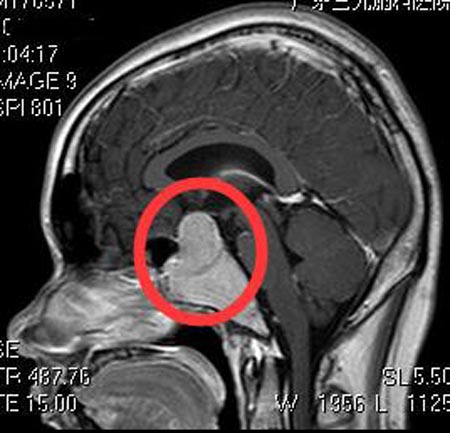

姐姐急急忙忙地带着小康在当地医院行头颅CT检查,提示:鞍区占位病变,考虑侵袭性垂体腺瘤。广东三九脑科医院垂体瘤诊疗中心进一步行头颅MR检查发现:鞍内及鞍上区示一不规则异常信号影,大小约3.8cm×4.2cm×6.2cm,考虑侵袭性垂体腺瘤可能性大。头颅CTA检查提示:斜坡-鞍区占位性病变,病变边缘有少许细小血管,并包绕右侧颈内动脉虹吸段。

鲁明主任告诉他们:垂体瘤如果出现眼睑下垂,一般属于周围结构受压症状,即肿瘤侵犯了垂体周围的神经血管丛海绵窦,引起眼睑下垂、瞳孔变大等表现。

完善术前检查后,由鲁明主任主刀,在全麻下行经鼻蝶蝶窦内及鞍区巨大垂体腺瘤切除术,显微镜下切除蝶窦内肿瘤组织,暴露鞍底及斜坡区,见鞍底破坏,导航再次定位双侧颈内动脉及垂体组织,切除鞍内、右侧海绵窦肿瘤。术后小康没有出现脑脊液漏、尿崩、离子紊乱的并发症,右侧下垂的眼睑恢复正常。术后病理结果提示:垂体腺瘤。